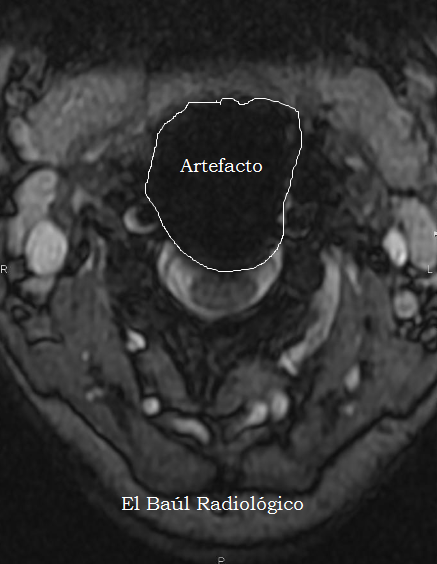

Los dispositivos más raros y variados que se suelen encontrar en cualquier imagen radiográfica, son los que utilizan los traumatólogos y neurocirujanos para estabilizar las vértebras de la columna lumbar. Como son de titanio no suelen contraindicar ninguna exploración de TRM. Tampoco se calientan, ni se mueven. En cambio, en los exámenes de TC producen numerosos artefactos radiales, como cualquier otro metal.

(The most rare and varied devices that we usually find are those used by orthopedic surgeons and neurosurgeons, to stabilize the vertebrae of the lumbar spine. Here are some very specific models of interspinous metal implants used in our hospital. Made of titanium, they not contraindicate any exploration of MRI. Neither heat, nor moved. In contrast, in CT examinations they produce many radial artifacts, like any other metal)

La mayoría de estos objetos están fabricados en titanio, material no ferromagnético, que no supone ningún peligro para las personas que se van a someter a una exploración de Tomografía por Resonancia Magnética (TRM). Sí, en cambio, provocan la aparición de artefactos por susceptibilidad magnética que impiden la correcta evaluación de la zona quirúrgica, lo cual supone un inconveniente. Cuando el material utilizado es de acero, los artefactos que aparecen son mayores. En este caso no hay que temer por las posible consecuencias porque es imposible que los tornillos de la artrodesis, correctamente insertados, sean removidos por la fuerza del campo magnético del imán. Otro efecto indeseable es el calentamiento del metal que se puede producir, cuando se realizan exploraciones muy largas. Hay que tenerlo en cuenta y ser resolutivos. Con dos o tres secuencias es suficiente para realizar un examen de TRM cervical.

(Most surgical devices in use today are made from titanium, non-ferromagnetic material, which poses no danger to people who are about to undergo a MRI exam. They provoke the appearance of magnetic susceptibility artifacts that prevent us the proper evaluation of the surgical site. When the material used is steel, the artifacts are greater. In this case it is impossible that arthrodesis screws are removed by the magnetic field strength of the magnet. Another effect indeseable is heating the metal, when scans are very long. This should be taken into account. With two or three sequences is enough to made an examination of TRM).